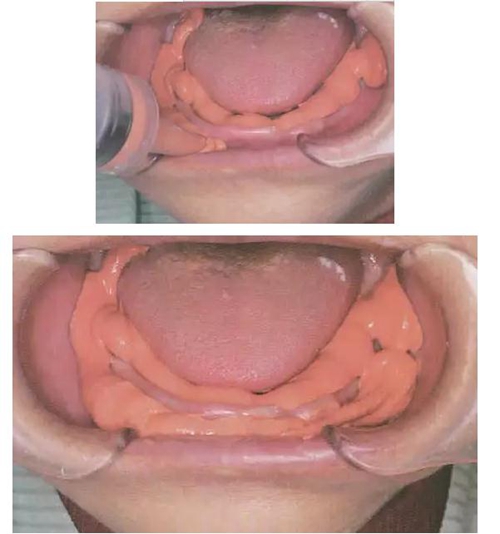

將FCB托盤放入口中,讓患者將舌頭放在托盤上,

然后患者慢慢閉上嘴,用嘴唇含住托盤柄,

停止閉合,在最放松的位置保持不動。

⑤ 重體托盤口內(nèi)就位

⑴ 平穩(wěn)地放入,將前牙部分壓向牙槽脊,將托盤的舌側(cè)翼緣區(qū)伸入下頜舌骨肌后窩區(qū),讓患者舌頭放在托盤上,并將托盤輕輕壓向下頜牙槽嵴,不可像傳統(tǒng)托盤大力壓向牙槽嵴,下頜牙槽嵴條件差時(shí),輕輕將托盤壓向牙槽嵴7-10秒后再要求患者閉上嘴,用嘴唇含住托盤柄。

⑵ 術(shù)者站在患者后方,用手輕輕推頰棚區(qū)向上。

以避免多余印模材在頰棚區(qū)滯留。